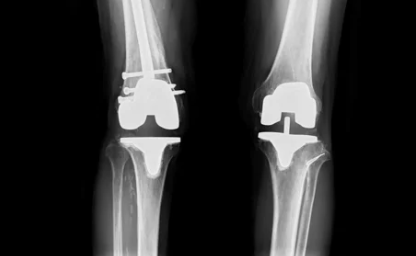

무릎 인공관절 수술은 손상된 무릎 관절을 제거하고, 이를 대신할 인공관절을 삽입하는 수술입니다. 주로 퇴행성 관절염, 연골 손상, 또는 무릎 관절의 기형으로 인해 무릎 기능이 심각하게 손상된 사람들에게 시행됩니다.

- 부분 인공관절 수술과 전체 인공관절 수술에 따라 비용이 다릅니다. 부분 인공관절 수술은 무릎의 일부만 교체하는 방법으로, 비용이 상대적으로 저렴할 수 있습니다. 반면에 전체 인공관절 수술은 무릎 전체를 교체하는 방법으로, 더 복잡하고 비용이 높습니다.